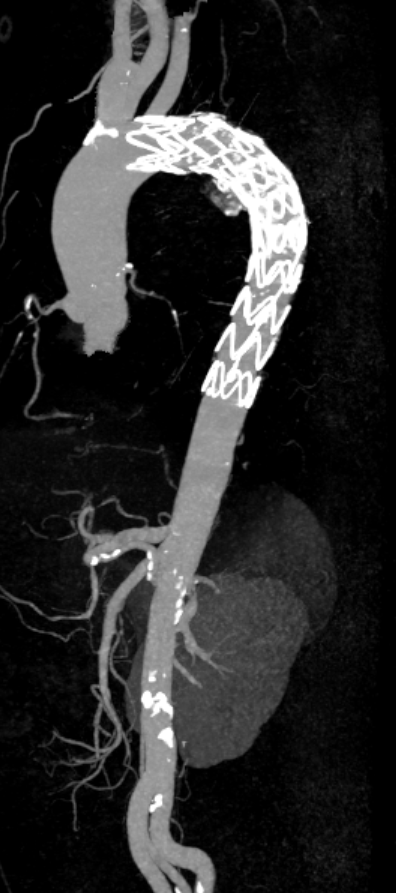

联系卒中中心医生会诊并收住院治疗,经专科查体发现患者T6脊髓节段水平以下痛温觉、触觉

明显减退,双侧巴氏征阳性。

这是一个典型的脊髓横贯性损害体征,提示病灶位于胸髓。加做胸椎+腰椎磁共振平扫

,仅发现广泛的退行性变和椎间盘突出,未见明确的脊髓肿胀、异常信号或占位性病变。(见图3、图4)

图3

图4